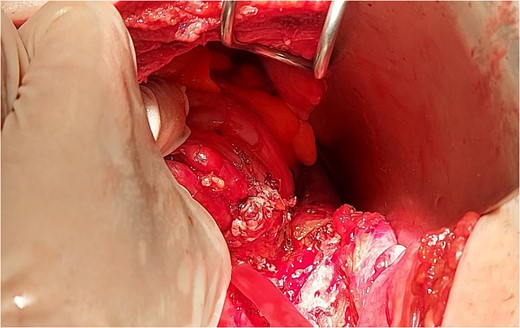

The intraoperative findings (Fig. 3) and the specimen (Fig. 4) show a spot in the sigmoid colon communicating with the left lumbar region. We performed a segmental resection and restored bowel continuity using a double stapling technique. We also placed a drain at the site of the previous lumbar incision. Pathologic examination of the resected colon revealed sigmoid diverticulitis and no histologic evidence of Crohn’s disease or actinomycosis (Fig. 5a and b).